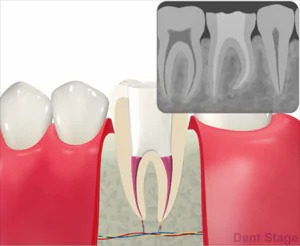

むし歯が深くまで進んで神経にまで達してしまった場合に行う治療で、歯の根の中をきれいに掃除して、ばい菌が入らないように薬を詰めて密閉します。歯の根っこの内部には、神経や血管が入っています。ここを根管と言います。

むし歯が進行して、根の中に菌が入ると汚れがたまります。汚れている根管を綺麗にするために、ファイルという器具で掃除し、消毒薬を使って汚れを洗い流し、治療と治療の間で菌を増やさない様に薬を詰めます。最終的に根管が綺麗になったら、細菌が繁殖しない様にお薬を詰めて終わりになります。この治療をしっかり行う事により、患者様の歯を更に長生きさせることができます。

むし歯が進行して神経にまで達すると、「冷たいものや甘いものがしみる」「温かいものでズキッと痛む」「噛むと痛い」などの症状が現れることがあります。さらに悪化すると、何もしていなくてもズキズキと痛みが出たり、歯ぐきが腫れたりすることもあります。このような状態になると、神経を取り除く「抜髄」や、すでに神経の治療をした歯に再び炎症が起きた場合は「再根管治療」が必要になることがあります。また、痛みが出ないまま進行しているケースもあるため、レントゲンなどでの定期的なチェックが大切です。